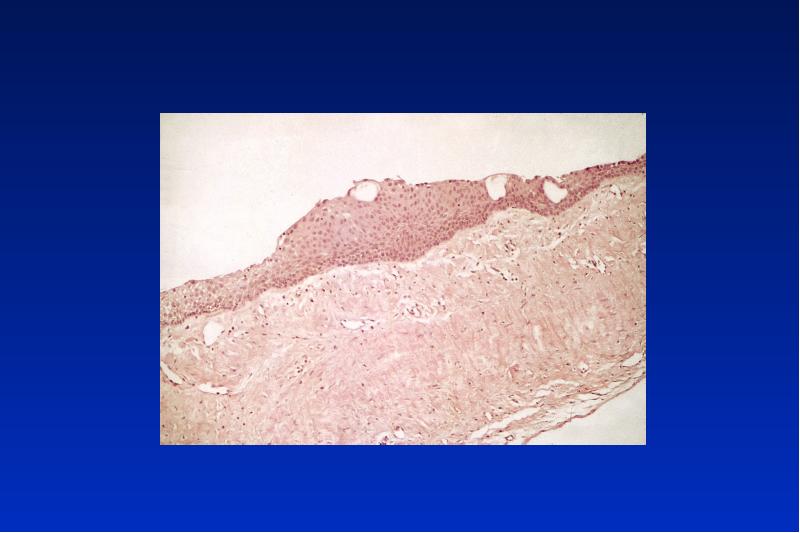

- 21. Odontogene Keratozyste Lok: UK Alter: 20 - 30, 50 - 60